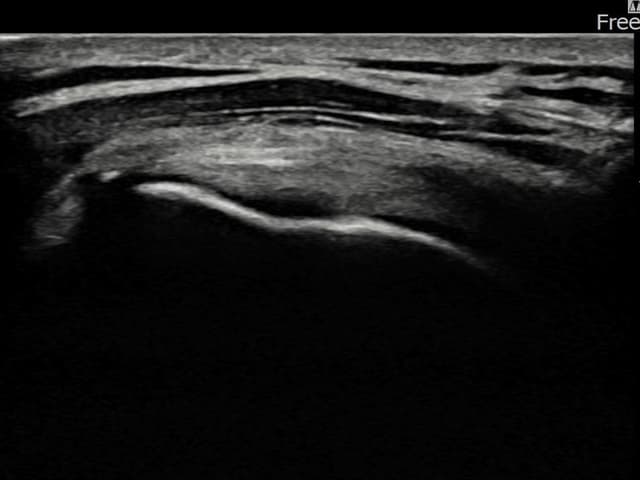

[촬영시기:24.01.25~24.04.03]

[어깨인대 축소봉합술] 좌측 어깨 부착부 통증과 야간 통증으로 수면 장애가 있어 내원하셨습니다.